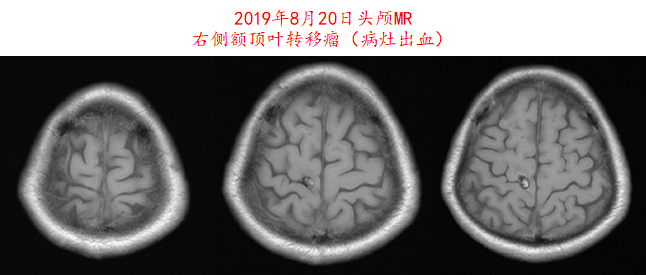

image009.png

图7.患者2019年8月20日头颅MR影像资料